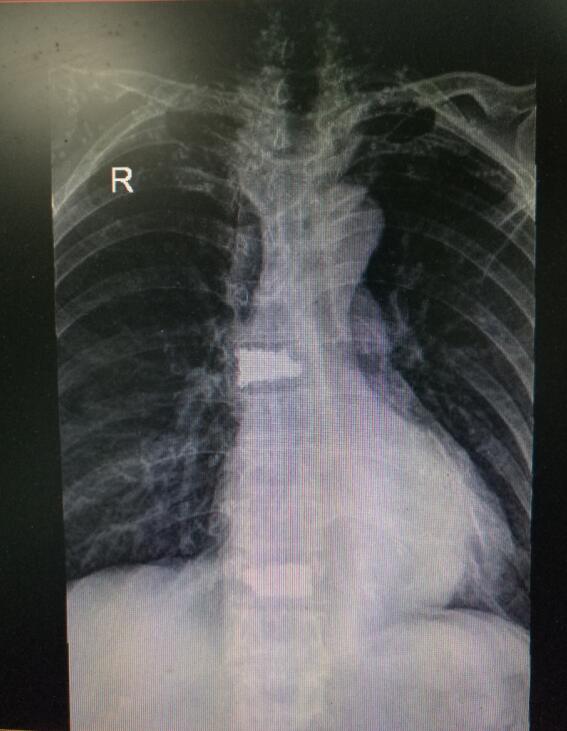

術(shù)后DR(數(shù)字化的x射線)

入院后第四天,由骨傷二科副主任楊陳一、劉永森醫(yī)生、唐國皓醫(yī)生聯(lián)合為患者成功實施了微創(chuàng)下的經(jīng)皮穿刺椎體后凸成形術(shù)。術(shù)后,患者腰背部疼痛逐漸緩解,術(shù)后第二天即下床活動。

“該微創(chuàng)術(shù)式主要針對中老年患者發(fā)生的胸腰椎壓縮骨折,具有創(chuàng)傷小、恢復(fù)快、術(shù)后第二天即可下床行走等優(yōu)勢,一般患者住院4—5天即可?!碧茋┽t(yī)生表示,考慮到該患者前后兩次骨折均無明顯誘因,背后主要的“元兇”在于其基礎(chǔ)疾病——骨質(zhì)疏松,在治療過程中,除了治療患者的骨折,術(shù)后醫(yī)生還采用院內(nèi)制劑壯筋補骨丸等,積極對其骨質(zhì)疏松進(jìn)行改善治療,增強其骨密度。經(jīng)過10余天的有效治療,現(xiàn)患者骨折已基本痊愈,骨質(zhì)疏松也得到了一定的改善,于12月12日康復(fù)出院。